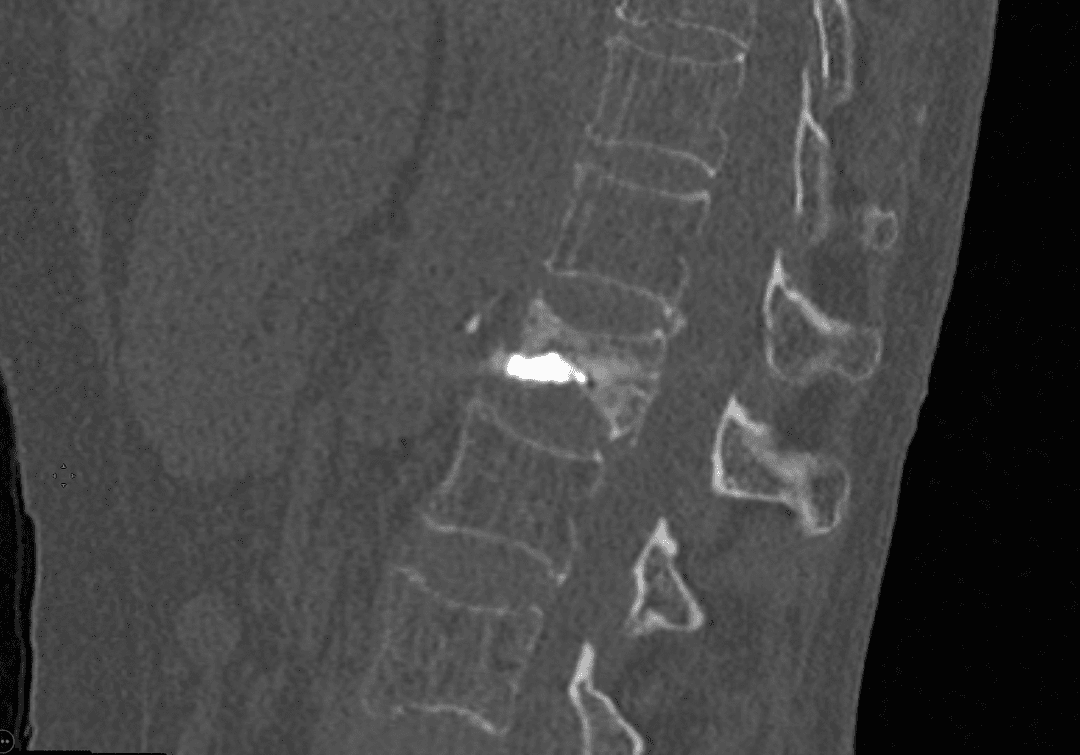

Positionnement de l'aiguille sous guidage

Guidage de l’aiguille

Grâce à des images en temps réel obtenues par fluoroscopie et/ou scanner, l’équipe médicale guide avec précision une aiguille jusqu’à la zone concernée, évitant ainsi les structures sensibles comme les vaisseaux sanguins.